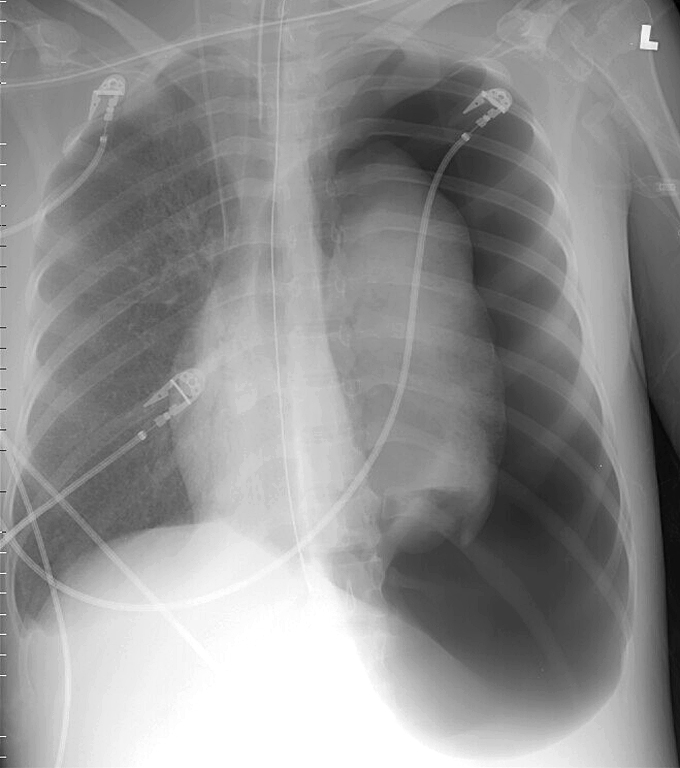

Gallery Blunt Chest Trauma Pneumothorax 10 tension

10 tension